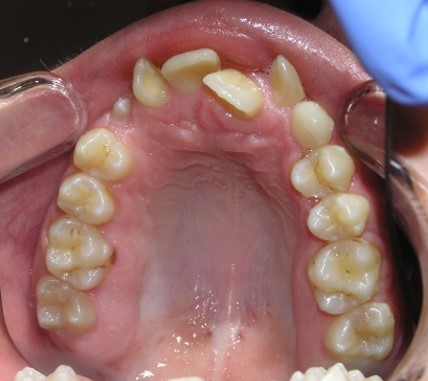

Palatal teeth position

Palatal position of teeth is

characterized by the eruption of one tooth or a group of teeth outside the

dental arc on the palatal side. So, most often, incisors or second premolars

eruption.